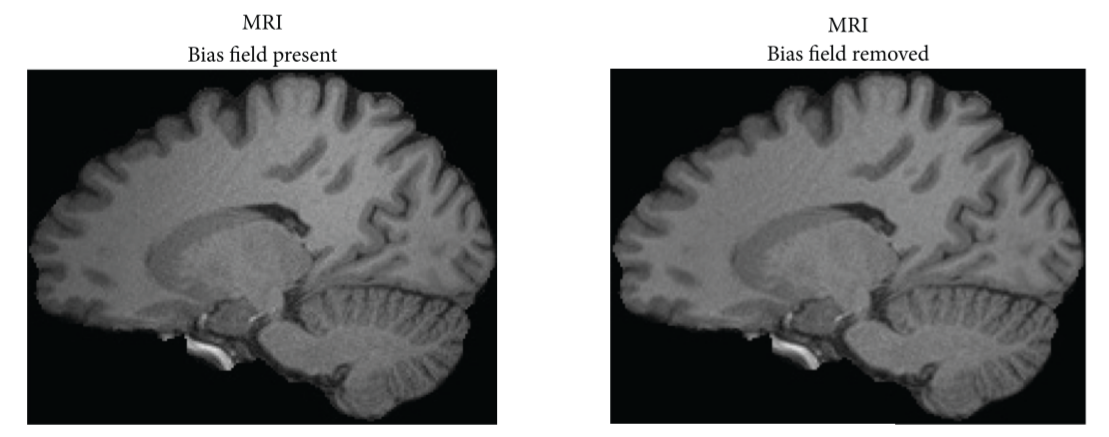

A bias field is a low-frequency signal which arises because of the fact that the magnetic field is not fully homogeneous inside the MRI scanners, but rather there are some small inhomogeneities, especially on the boundary of the scanner. If the image for the analysis is not preprocessed in a way to reduce the effects of the bias field, the performance of segmentation (and thereby all the later analyzing steps) is affected. Figure 3 shows the segmentation of the image with and without bias field removal.

To make the network adaptable to bias field effect, SynthSeg artificially modifies the training images, so that they act as if the effect were present. The modification is done in the following way: first, the low-resolution 4x4x4 matrix is sampled from a normal distribution with zero mean. Then, it gets upsampled to the resolution of the training image and exponentiated afterward (which ensures that all the values of the matrix are positive). Finally, the image is multiplied with the matrix

Fig 3. The comparison of the segmentation with and without the presence of bias field. Image source: [5]